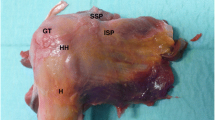

The paired specimens (n = 24) originated from eight male and four female donors(Fig. 1). Mean donor age was 79 years (range 66–99). The peroneus brevis muscle was visualized through a lateral incision, then it was carefully dissected from its origin and followed distally to the insertion at the proximal aspect of the fifth metatarsal [18]. Care was taken to prepare the whole muscle belly with the intact tendon. The PBT insertion was not touched, and the fifth metatarsal was disarticulated from surrounding joints and liberated from soft tissue. Specimens were kept moist with saline solution to prevent tissue desiccation throughout the preparation process. Each specimen was screened for any evidence of previous open peroneal tendon surgery or Jones fracture fixation. Following inspection of the specimens, all pairs proved valid for the study and thereafter were assigned to two matched pair groups comprising an equal number of left and right feet for Jones fracture creation. The fifth metatarsal bone was distally fixed in a padded machine vise during fracture creation and preparation for intramedullary screw fixation (Fig. 2). A longitudinal line was drawn on the metatarsal in order to check for the rotational alignment. To simulate a Jones fracture (zone II), a complete transverse fracture at the meta-diaphyseal junction at the distal aspect of the fourth to fifth intermetatarsal articular facet was created with an oscillating saw. The proximal part of the bone was held in place with a small forceps during intramedullary screw preparation and placement. One group underwent intramedullary fixation with a Jones fracture-specific screw (Jones Screw; Arthrex Inc., Naples FL, USA) (JFXS group), while the other group was stabilized with a conventional cannulated headless compression screw (HCS; DePuySynthes, Solothurn, Switzerland) (HCS group). Screw size was determined upon the “fit and fill” principle. The intramedullary screw had to “fit and fill” the medullary canal with the threads across the fracture site. HCS were available in diameters 4.5-mm and 6.5-mm, and Jones Screws were used in diameters 4.5-mm and 6.0-mm. Small matched pair specimens (3/12) received 4.5-mm JFXS or HCS, and large specimen pairs (9/12) received 6.0-mm JFXS or 6.5-mm HCS.

Bony cut out of the proximal screw head was the most common mode of failure among HCS constructs (n = 6; 50%), followed by fracture of the metatarsal at the level of embedding in the steel cup (n = 4; 33%) (Supplementary Video 1). In JFXS constructs, the most common mode of failure was classified as fracture of the metatarsal at the steel cup (n = 5; 50%) followed by a bony cut out of the screw head (n = 3; 30%) (Fig. 5). No screw bending or screw breakage was observed.